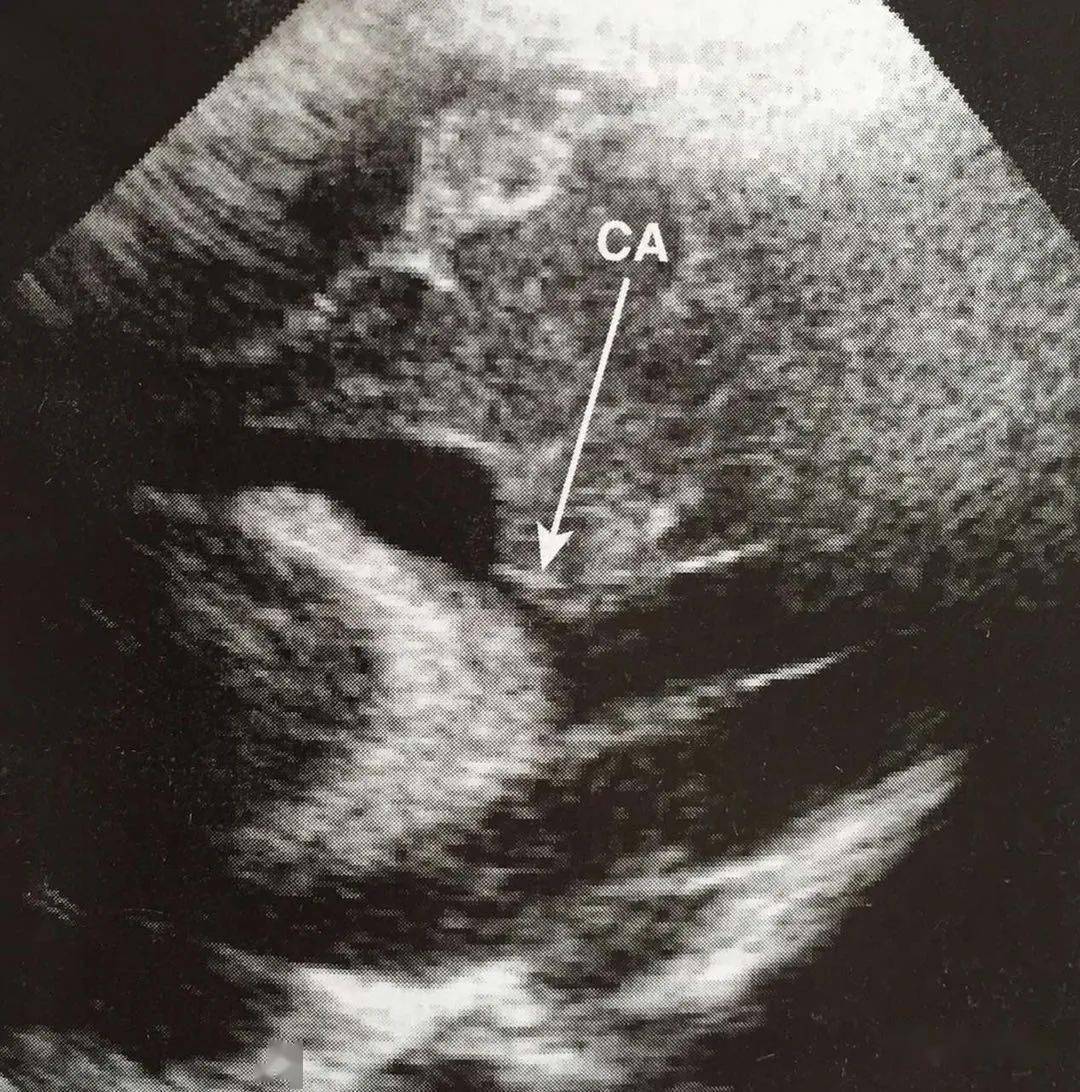

胎儿侧脑室超声图片,胎儿侧脑室测量图片

【新手必看】中孕期胎儿超声检查 — 颅脑和颜面部分

(图2) 图2 当出现脑室扩张时,胎儿需要接受详细的超声检查或进一步行

图2 患者女,33周早产,超声图像示左侧侧脑室强回声出血灶,脑室可见

胎儿脉络丛声像图_脑室